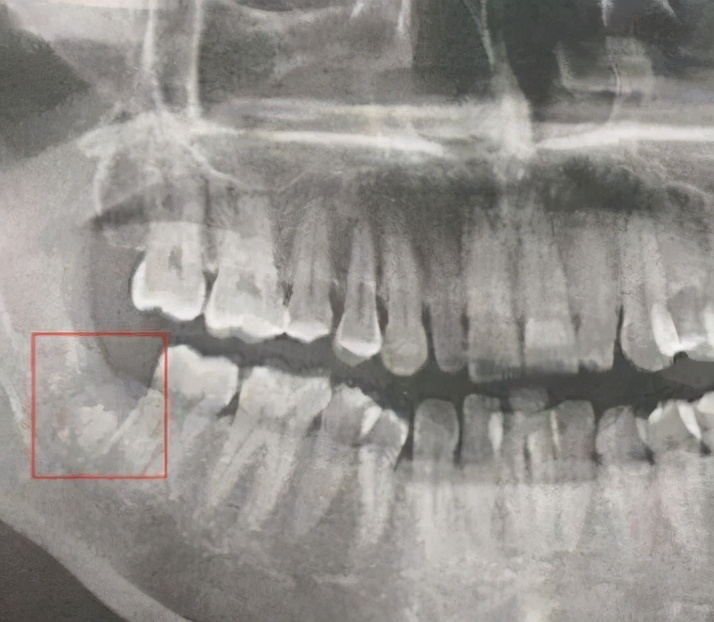

发生率:下颌阻生智齿拔除后>下颌第三磨牙>下颌第一磨牙>下颌第二磨牙,别的牙很少见,前牙发生率最低。

拔牙后,牙根原来所在的牙槽窝,应该由血凝块充满而后渐渐愈合,由于种种原因导致拔牙后2~4天牙槽窝内血凝块分解、破坏、脱落、感染而导致拔牙窝骨壁暴露并发生多处小的骨质坏死灶,可出现碎小的死骨。